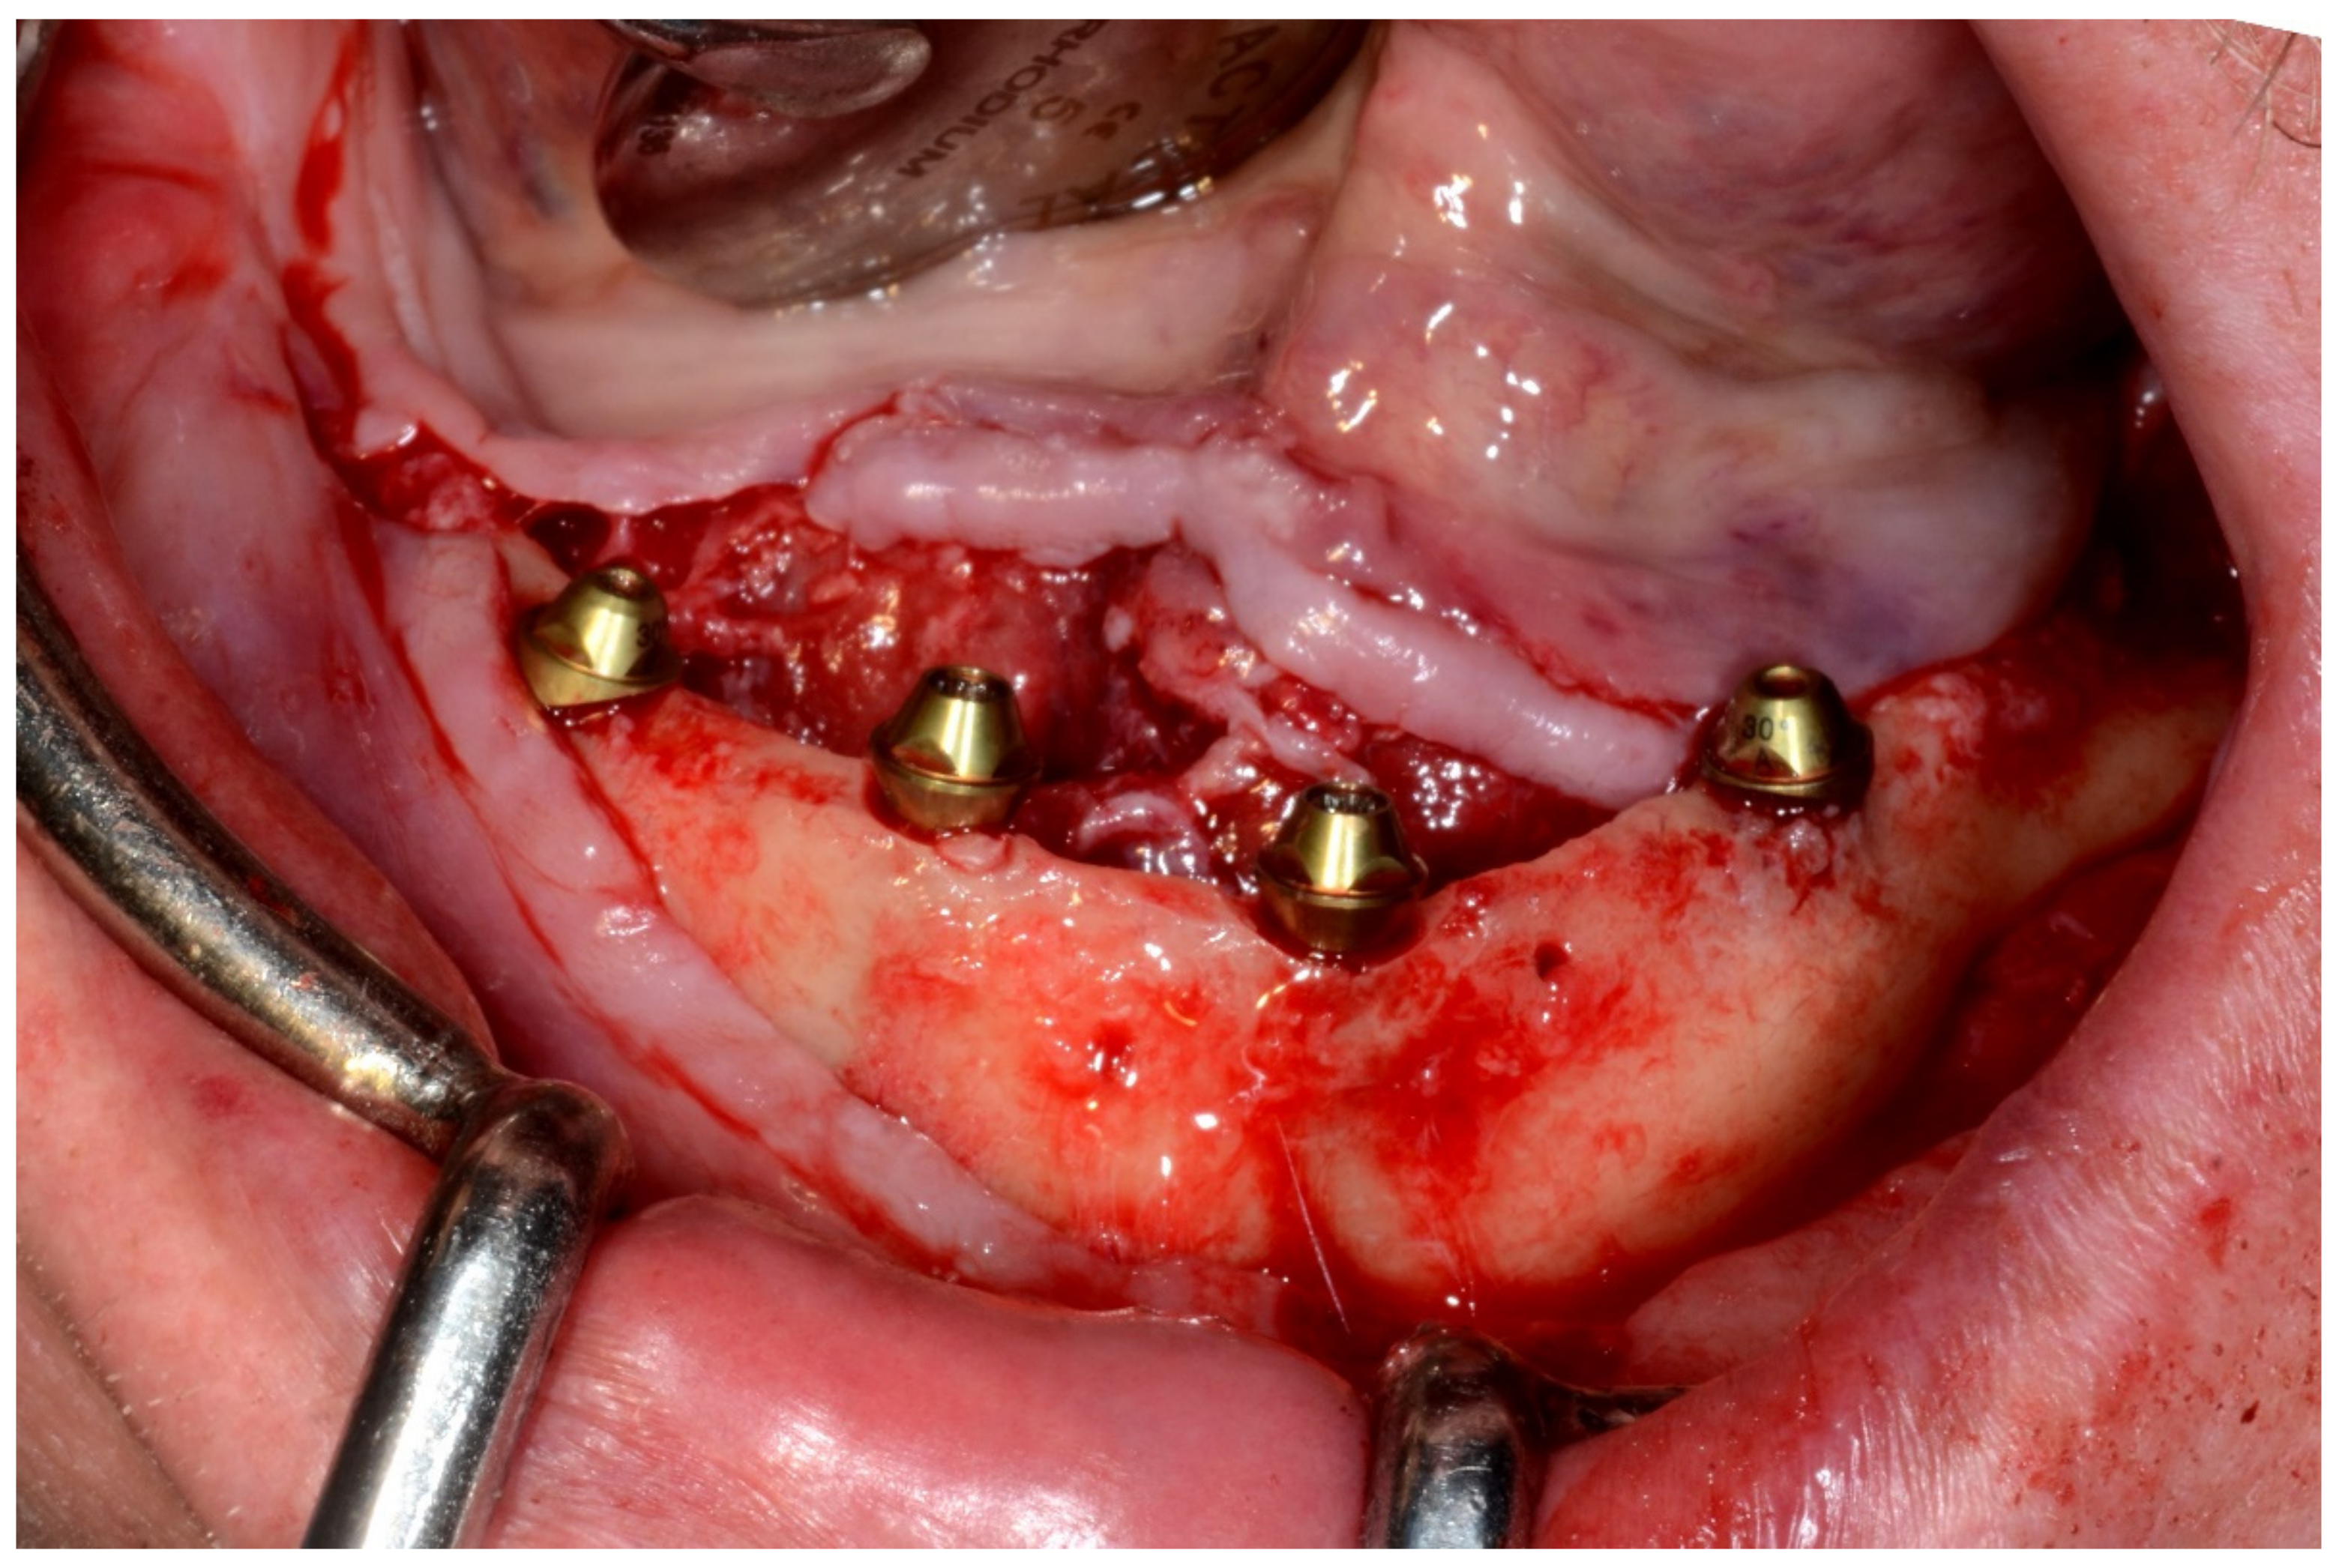

6.2.4. Intra-Operative Documentation:

In March 2013, twelve guided dental implants were placed at sites # 12, # 13, # 15, # 22, # 23, # 25, # 33, # 34, # 36, # 43, # 44, and # 46 (Figure 22, Figure 23, Figure 24, Figure 25 and Figure 26)

Figure 22.

Maxillary surgical drilling guides temporarily supported and fixed with mini-screws.

Figure 23.

Mandibular surgical drilling guides temporarily supported and fixed with mini-screws.

Figure 24.

Implant bed preparation using guided drills inserted into specific ad hoc drill handles.

Figure 25.

Guided implant insertion.

Figure 26.

Mandibular implants in place.